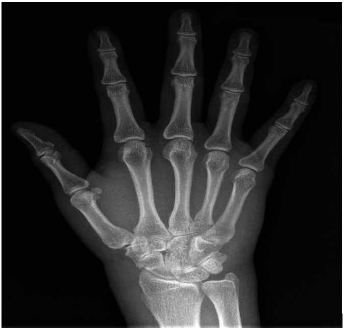

Los paraclínicos iniciales muestran leucocitosis con neutrofilia y PCR (Proteína C reactiva) elevada, resto de límites normales (Ver tabla 1). Se amplían estudios con perfil infeccioso, metabólico y autoinmune dentro de límites normales excepto por un factor reumatoide positivo; radiografía de tórax dentro de límites normales y radiografía de manos sin alteraciones óseas con edema de tejidos blandos (Ver imagen 2). El rastreo microbiológico solicitado al ingreso da preliminar a las 29,7 horas de morfología indeterminada, con cubrimiento antibiótico empírico con ampicilina sulbactam a dosis de 3 gramos cada 6 horas.